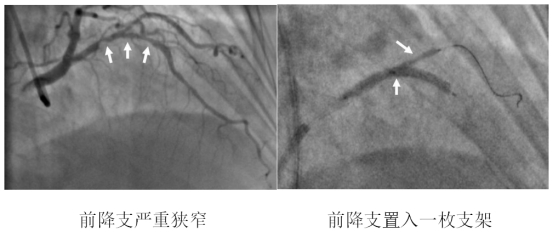

术中,造影结果与术前判断一致,患者前降支血管重度狭窄且病变累及较大分支血管开口,需要介入治疗。公永太教授带领介入团队,凭借精湛的手术技巧,首先分别于前降支及分支送入导丝,在分支预埋球囊保护下,于前降支病变部位置入一枚支架,之后再送入导丝穿支架网眼至分支内,完成球囊后扩张和对吻扩张。操作过程中采用IVUS评估病变、优化支架置入,全程未使用对比剂。整个手术的对比剂用量不足15ml,远远少于一例普通患者单纯造影所用剂量。患者术后复查肌酐无增高,心绞痛症状完全缓解,顺利出院。

IVUS示支架贴壁、膨胀良好